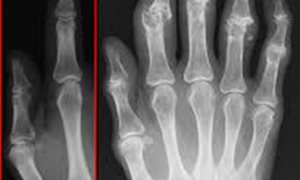

Artrose is een reumatische aandoening waarbij het kraakbeen in de gewrichten dunner en zachter wordt. Dit geeft een pijnlijk en stijf gevoel in de gewrichten tijdens beweging. Hoewel eerst gedacht werd dat de oorzaak gewrichtsslijtage is, wordt steeds duidelijker dat ook ontstekingsprocessen en de stoffen die daarbij vrijkomen bijdragen aan de ernst van artrose. Daarnaast groeit het bewijs dat er een verband is tussen hoge cholesterolwaardes en ontstekingsziekten. Wouter de Munter onderzocht daarom de rol van cholesterol bij artrose in muizen.

De Munter bekeek muizen die een cholesterolrijk dieet kregen en muizen die van nature hoge cholesterolwaardes hebben. Beide muizen ontwikkelden extra botvorming in het door artrose aangedane gewricht, wat leidt tot pijn en functiebeperking van het gewricht. Bepaalde afweercellen, macrofagen, bleken verantwoordelijk voor de extra aangroei van bot. De Munter: “Als geoxideerd LDL wordt opgenomen in macrofagen, activeren macrofagen groeifactoren die van nature veelal inactief aanwezig zijn in het gewricht. Activatie van groeifactoren kan stamcellen in het bot aanzetten tot het vormen van kraakbeen en bot.”